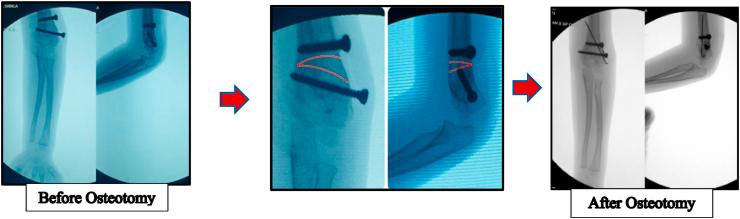

Two cases of malunited supracondylar humerus are described. The first case involves a 3-year-old girl who presented with outstretched and supinated left arm after falling during bike riding 3 weeks earlier. We found no abnormality in radial and median nerve function, but the left arm radiographs showed a callus formation and the early stages of a malunited fracture of the supracondylar humerus. We waited two months for further radiographic evaluation and the radiographs showed the malunited supracondylar humerus with elbow flexion of only 105° and elbow hyperextension of 20°. The cubitus varus was recorded with clinical carrying angle of varus 10°. We used a combination of original French and Dome osteotomy, lateral approach, and our novel fixation technique with excellent results. The second case involved a 8-year-old boy with malunited right elbow and the surgery was done in the same manner, with the result of restoration to normal elbow range of motion. We also assessed the pain score and disabilities of the arm, shoulder and hand (DASH) score and recorded satisfactory results.

描述了两例肱骨髁上骨折畸形愈合的病例。第一例是一名3岁女孩,3周前骑自行车摔倒后出现左上肢伸直旋后位。我们发现桡神经和正中神经功能无异常,但左上肢X线片显示有骨痂形成以及肱骨髁上骨折畸形愈合的早期阶段。我们等待了两个月进行进一步的影像学评估,X线片显示肱骨髁上骨折畸形愈合,肘关节仅能屈曲105°,过伸20°。记录肘内翻时的临床携物角为内翻10°。我们采用了原创的法国截骨术和圆顶截骨术相结合、外侧入路以及我们新颖的固定技术,取得了优异的效果。第二例是一名8岁男孩,右肘畸形愈合,手术方式相同,结果恢复了正常的肘关节活动范围。我们还评估了疼痛评分以及上肢、肩部和手部功能障碍(DASH)评分,结果令人满意。